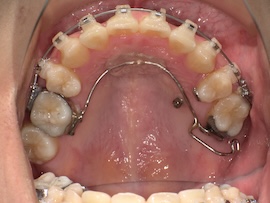

左上の7番目を抜歯してから約9ヶ月が経過しましたが、代わりに活かしていきたい親知らずが出てこないのでついに牽引(歯茎を切って引っ張り出す)をすることになりました。

内側の装置が新しくなるので今回は型取りをして準備を進めていきます。

右上の6番目にバンド(金属の輪っか)を装着するためブラケットは一時的に外しています。

左上の奥に打っていた矯正用アンカースクリューですが、今回も安定せず揺れてきてしまったので抜くことになりました。

ある程度噛み合わせは良くなってきたのであとはゴムかけだけでも問題ないとのことです。